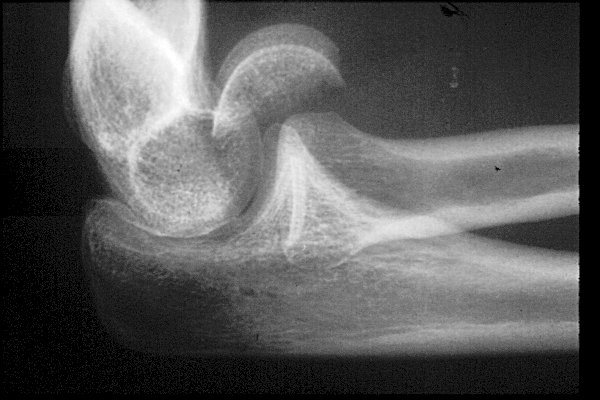

Return to Capitellum Fracture